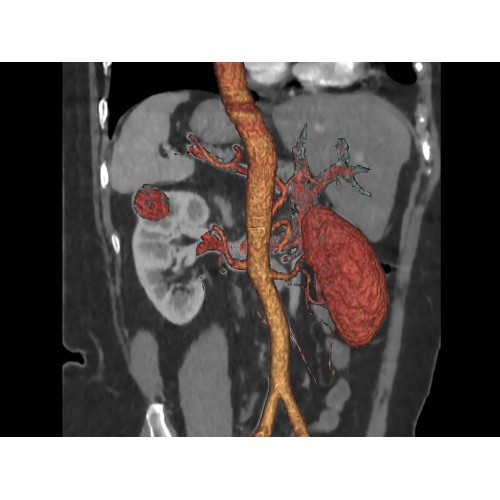

Кардиология

• Неинвазивная оценка состояния коронарных артерий.

• Диагностика атеросклероза и других сердечно-сосудистых патологий.

Онкология

• Раннее выявление новообразований и контроль эффективности лечения.

• Планирование лучевой терапии с высокой точностью.